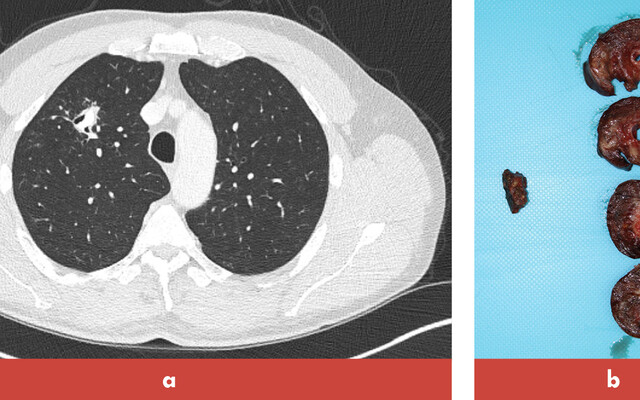

Op de polikliniek Longziekten zagen we een 30-jarige man wegens hoesten, dyspneu en vermoeidheid sinds een paar weken. Patiënt heeft 5 pakjaren gerookt en rookte nog steeds. Bij lichamelijk onderzoek en laboratoriumonderzoek vonden wij geen afwijkingen. De thoraxfoto toonde nodulaire afwijkingen, diffuus verspreid over beide longen (figuur 1). Aanvullend werd een CT-thorax verricht waarop diffuus verspreide, deels caviterende noduli over alle longvelden werden gezien (figuur 2). Bronchoscopie leverde geen diagnose op. Omdat de differentiaaldiagnose nogal uitgebreid was en de patiënt snel duidelijkheid wilde, onderging hij een video-geassisteerde thoracoscopie (VATS) met wigresectie van de linker bovenkwab. Histopathologisch onderzoek liet scherp…